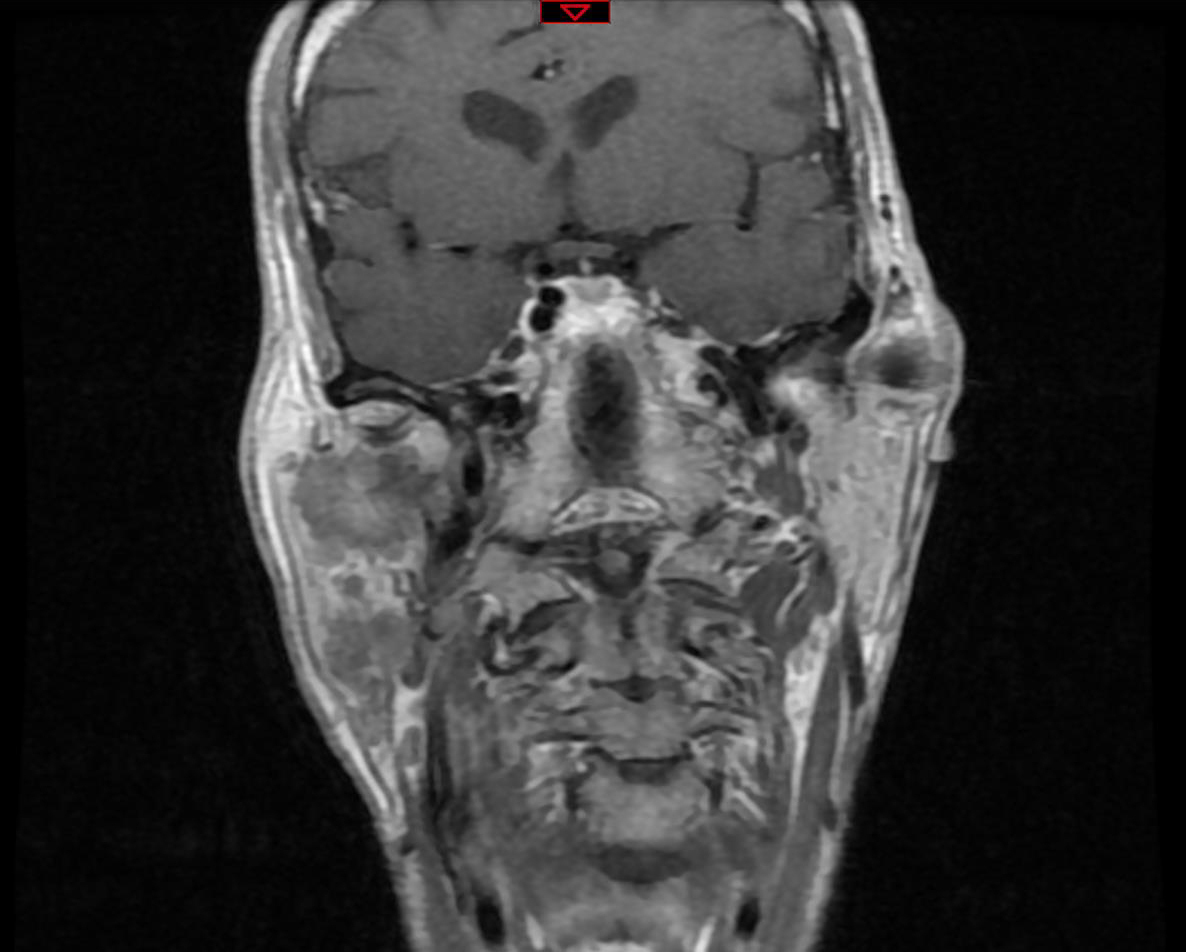

Dr Lanciaux-Lemoine, chirurgie maxillo-faciale, CHU Pitié-Salpêtrière, La Revue du Praticien IRM, coupe transversale, séquence T1, lésion mal limitée parotidienne droite, iso-signal T1.